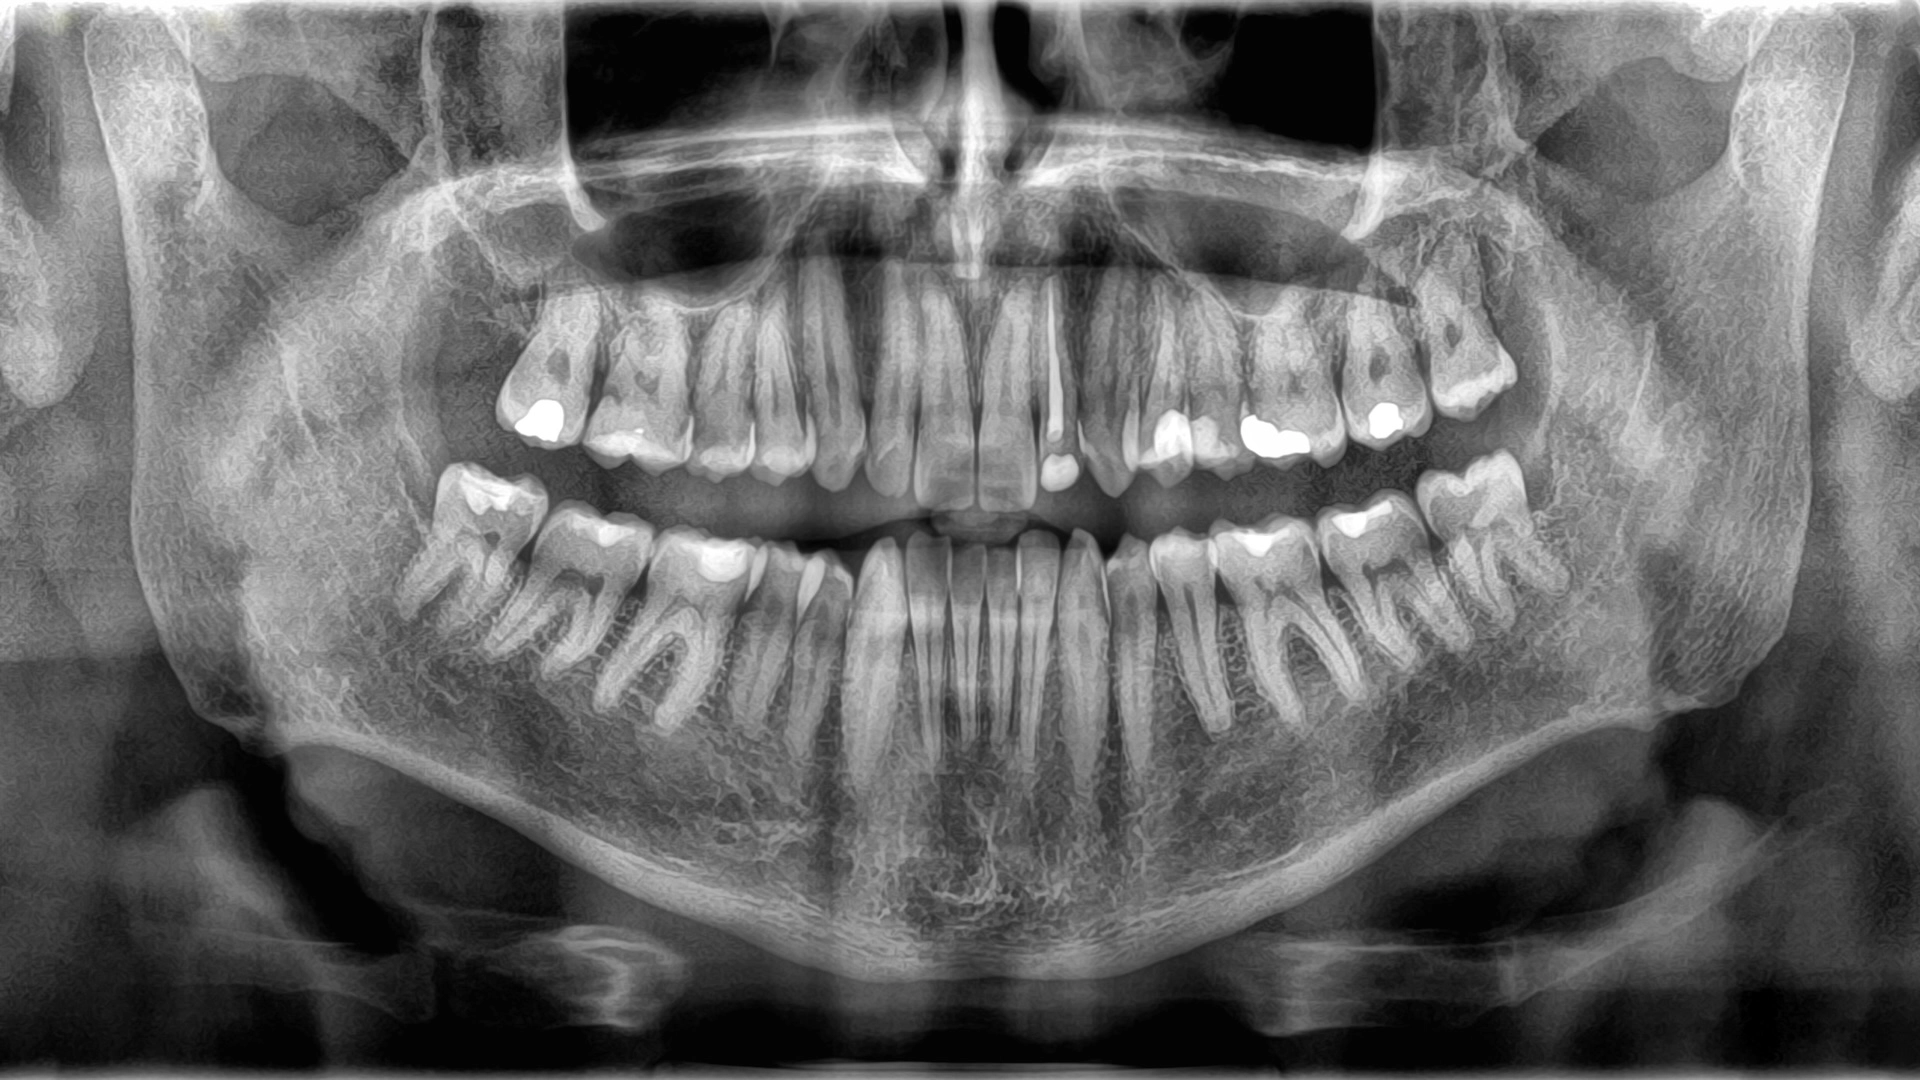

At first glance, teeth look a lot like bones: Both are hard, white and rich in calcium. So why aren't teeth considered part of the skeletal system? Even though teeth and bones share a few basic similarities, they're actually quite different.

The major resemblance between teeth and bones is what they're made of: hard tissue composed of minerals, such as calcium, phosphorus, fluoride and magnesium. On a molecular level, these minerals form a solid crystal structure, which is what makes both teeth and bones so much harder than everything else in the body.

Because bones and teeth do different jobs, they're also built differently. The outer structure of teeth is called enamel, a thin layer of mineralized tissue. Enamel is the hardest substance in the body — a property it gets from jam-packed crystals made from a compound of calcium and phosphate.

Underneath the enamel lies dentin, a type of mineralized tissue that's slightly softer than enamel but still hard. Dentin makes up the majority of a tooth's structure, and it contains tiny tubes that hold blood vessels and nerve endings. The core of the tooth is made of a jelly-like substance called pulp, which houses more blood vessels that provide nutrients to the tooth and to the nerves that control feeling in the tooth.